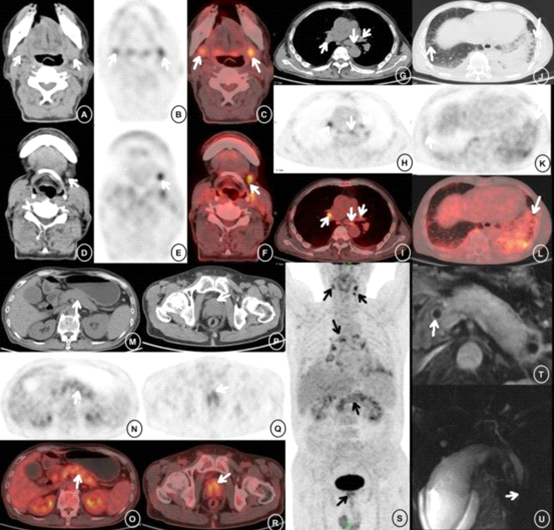

AIP患者,男性, 71岁,上腹部不适3个月,肿瘤指标升高(CA19-9:266.30 U/mL, CA125: 55.24 U/mL)。PET/CT显示:双侧下颌下腺肿胀,FDG摄取增高(图A–C);左侧颌下淋巴结增大,FDG摄取增高(D—F),纵隔及肺门淋巴结高代谢(G–I),两肺间质性炎症伴胸腔积液(J–L),胰腺肿大弥漫性FDG摄取增高(M–O),前列腺倒“八字形”高代谢灶(Q、R),全身PET投影图像(S);PET/CT同时显示胰腺及胰腺外病灶,对AIP诊断有独到价值。MRI增强延迟期显示胰腺均匀一致强化,周围低信号环状包膜样结构,胆总管上段轻度扩张,管壁增厚(T);MRCP显示胆总管下段狭窄,胆囊增大,胆囊窝积液(U)。